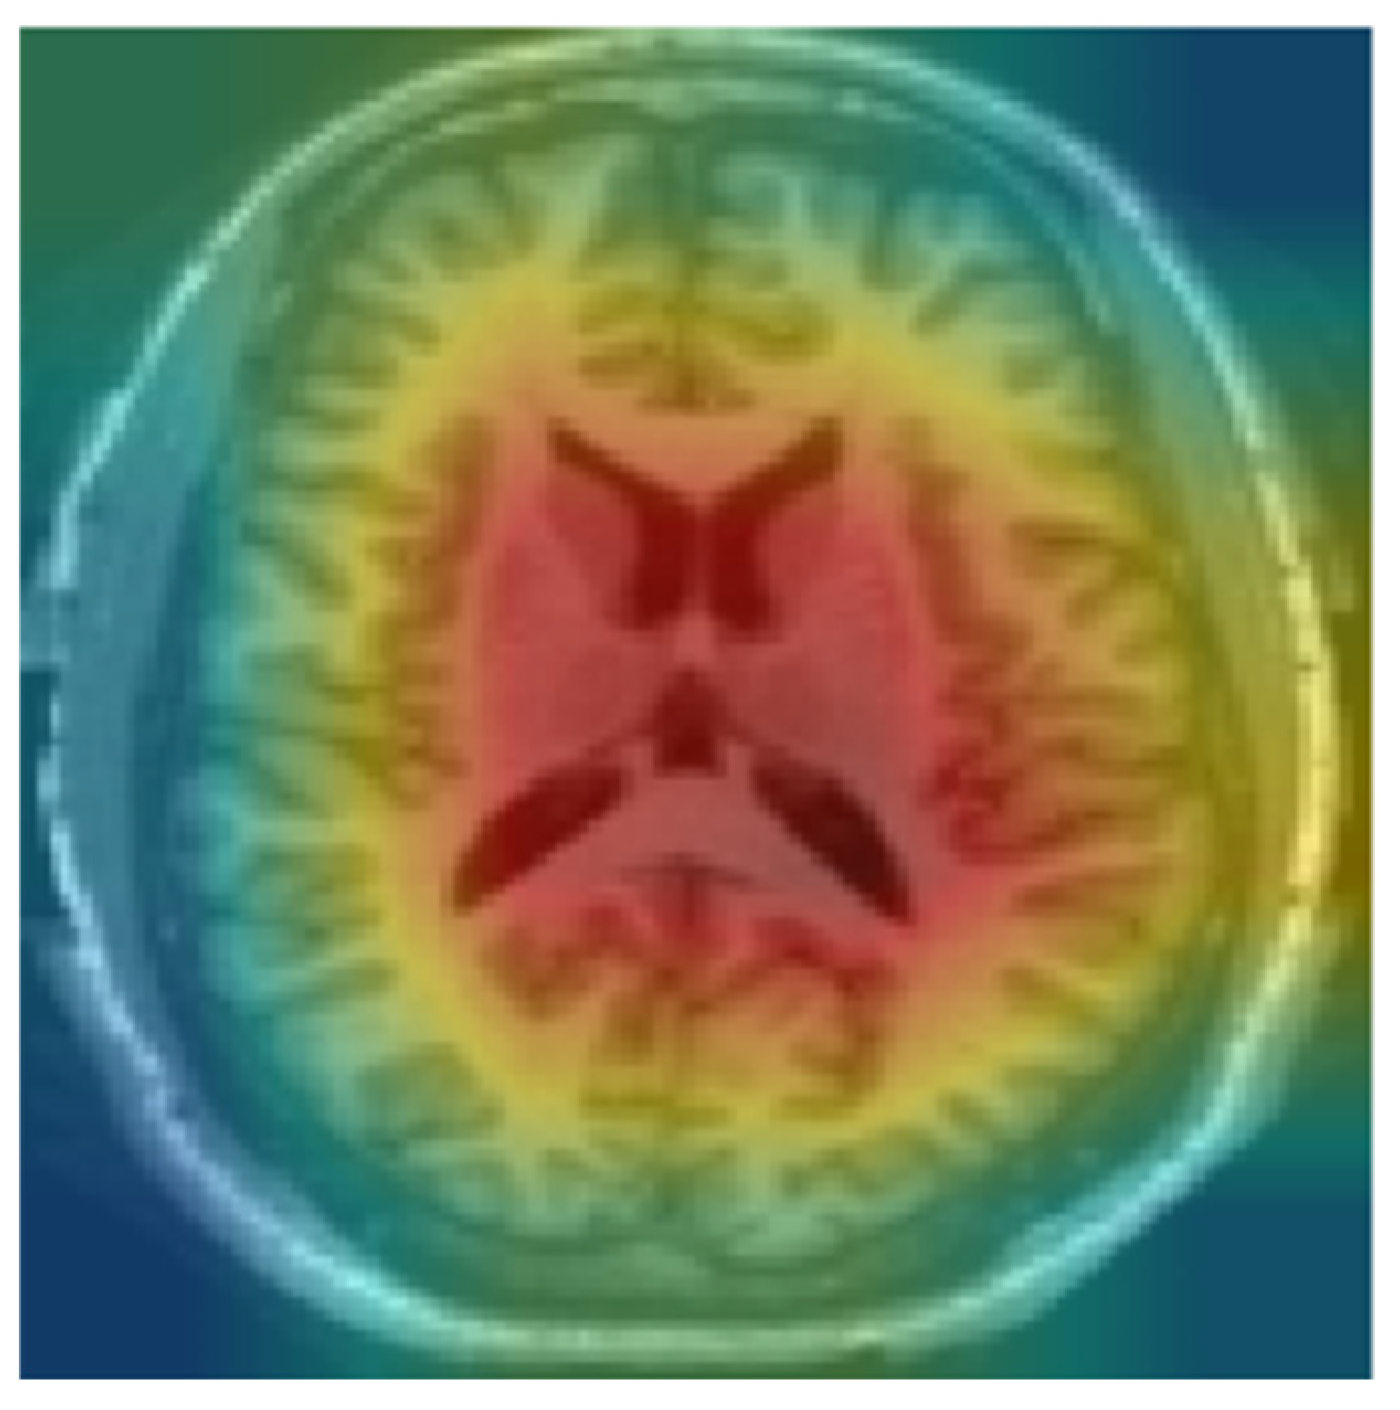

In contrast, by limiting the analysis to the middle slices that capture diagnostically relevant brain structures, our model provides more focused and clinically useful interpretations. By focusing on a limited number of segments with diagnostic information, we sought to reduce noise and improve the interpretability of the model’s decision-making process. This strategy simplifies the explanation of predictions, as it becomes easier to visualize and understand which parts of the image contribute to classification, especially when combined with visual annotation techniques. Figure 3 shows an MRI scan of the brain in the axial (horizontal) plane (A). The slices selected (B) are mid-brain slices, specifically at the level of the ventricles. These slices clearly show the lateral ventricles, the fluid-filled spaces in the brain. These mid-slice slides are critical for diagnosing neurodegenerative diseases such as AD, where enlarged ventricles are often associated with brain atrophy. Selected slides are then fed for training and testing (C). The model provides more focused and clinically useful interpretations by restricting training to the middle, diagnostically relevant slides (D).

Figure 3. Axial brain MRI at the ventricle level. We use only these mid-slice slides instead of full MRI scans to improve explainability and reduce the “black box” nature of AI models. (A) MRI visualization, (B) mid-slice selection, (C) model input, (D) anatomical interpretability enhancement.